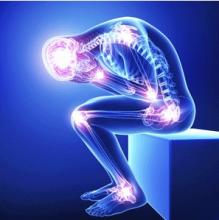

Actualité publiée il y a 10 années 2 moisDOULEUR CHRONIQUE: Elle dévaste le cerveau et le système immunitaire

Actualité publiée il y a 10 années 2 mois